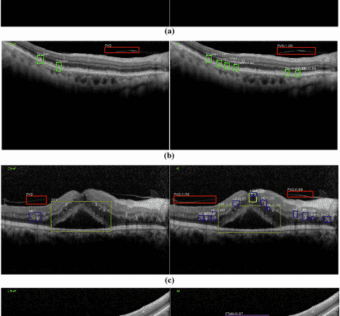

![]() An artificial intelligence cloud platform for OCT-based retinal anomalies screening system in real clinical environments

npj Digital Medicine - (Friday August 29, 2025) Millions of individuals worldwide suffer from retinal anomalies, which can lead to irreversible vision loss. However, the number of ophthalmologists is highly mismatched with the population base in China, especially in many rural and… ![]() News 8/29/25